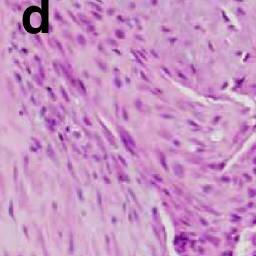

The histologic hallmark is calcifications seen in conjunction with an otherwise unremarkable fibrosing disease. Stippled calcification may be visible radiographically. Nuclei are large and darkly staining. Calcification may not necessarily occur in younger infants.